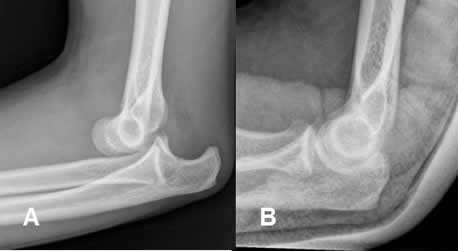

Fig 103. Técnica combinada.

A: Rx AP y B: Rx lateral. Fractura del olécranon, estabilizada con agujas y alambres.